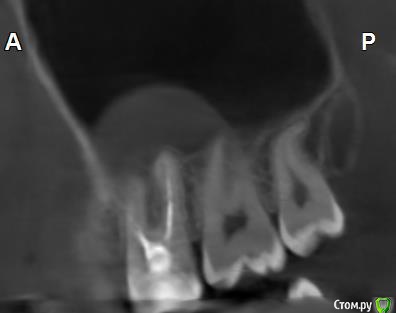

Здравствуйте! Верхний правый шестой зуб пломбировали 3 месяца назад. Примерно месяц назад он начал ныть, после насморка, сначала периодами, а теперь почти постоянно. При постукивание (ощущается не совсем так, как другие зубы) и пальпации десны он не болит. 2,5 месяца назад удаляли кисту из гайморовой пазухи. Может ли быть это какое-то воспаление и есть ли вероятность устранить его какими-нибудь антибиотиками, если да, то как, или может удалить зуб? Если есть воспаление, то какие могут быть последствия если не удалить зуб?

(Снимки с КТ, первые 8(Image) - сделаны сейчас,по 4 в разных проекциях, вторые 8(Before) - сделаны 5 месяцев назад до удаление кисты и повторного пломбирование зуба( до повторного пломбирование он реагировал на горячее, был запломбирован 3 года))

переличили зуб адекватно, во всяком случае по снимкам